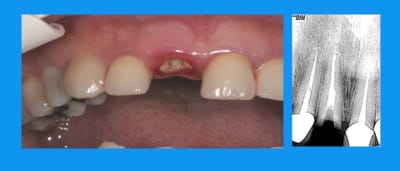

11 a du en passer par l'odf

non la patiente détestait ses diastèmes inf(microdontie relative des inc)

l'IC est scellé definitivement au fuji+

la provisoire au durelon (liquide thin)

traction en 3 mois

normalement la contention doit être laissée en place 3 mois minimum

cela dit ds ce cas,un ttt odf pr les incisives du bas ayant été entrepris,elle est restée plus longtemps

pr repondre à noa... ce n'est pas moi qui fais l'odf,je me suis contentée de demander,puis de travailler en parrallèle et de concert